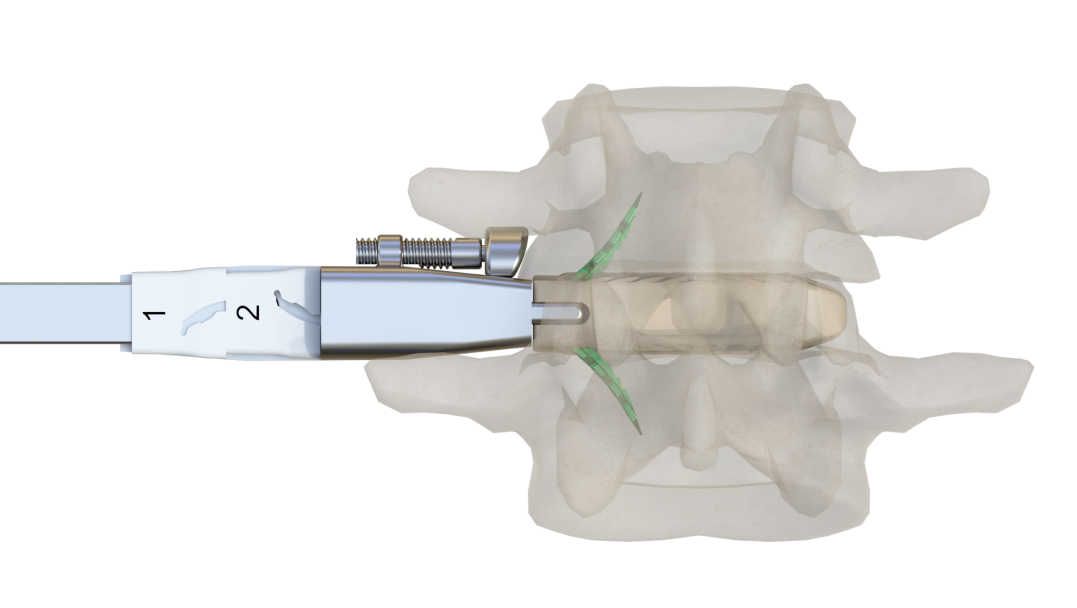

預彎的固定夾設計,交叉式自導(dao)向打入

根(gen)據不同椎體(ti)高度,選(xuan)擇合適的(de)固定夾

固定夾(jia)自限位設計,確(que)保(bao)打入(ru)后穩定性

固(gu)定夾敲入即(ji)鎖緊,操(cao)作(zuo)更簡單

固(gu)定(ding)夾(jia)可(ke)使責任椎(zhui)間隙術后得到即刻(ke)穩(wen)定(ding),通過固(gu)定(ding)夾(jia)將(jiang)融(rong)合(he)器與上下終(zhong)板錨(mao)定(ding),增加了固(gu)定(ding)和負載界面(mian),不(bu)但可(ke)防止(zhi)融(rong)合(he)器移位(wei),還(huan)可(ke)分擔椎體終板應力,減少融合器下沉的發生率(lv)。